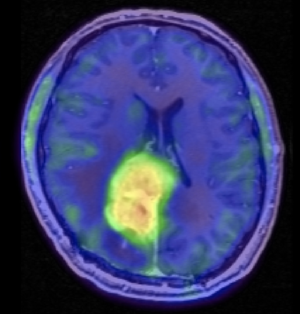

PET-scanning er en forkortelse for positron-emissions-tomografi. Siden slutningen af 1990'erne har PET-scanning især vist sig klinisk anvendelig inden for diagnostik og behandling af kræft. Til påvisning af kræftsvulster anvendes helt overvejende et sporstof (18FDG), hvor en radioaktiv fluorisotop er bundet til sukkermolekylet deoxyglukose. Kræftceller optager sukker hurtigere end normale celler, og derfor vil koncentrationen af radioaktivitet være størst i kræftcellerne. Den efterfølgende billedoptagelse med en PET-scanner vil da vise svulster og metastaser som lysende pletter.

PET-scanning anvendes til bestemmelse af en kræftsvulsts størrelse og udbredelse, til vurdering af, om en behandling har effekt, og til opfølgning med henblik på, om en kræftsygdom er brudt ud igen. En række andre sporstoffer er under udvikling for at øge den diagnostiske sikkerhed ved mistanke om kræft, fx 18fluor-tyrosin, 11carbon-methionin og 11carbon-cholin. Vid en række hjernetumorer anvendes FET-PET, hvor sporstoffet er (18)F-fluoro-ethyl-tyrosine.

Senest er PET-scanning blevet kombineret med CT-scanning i en såkaldt PET/CT-scanner. Man kan således med PET-scanning påvise en kræftsvulst og med CT-scanning nøjagtigt bestemme dens lokalisation.

Til diagnostik af hjernesvulster anvendes PET-scanning kombineret med MR-scanning af hjernen, hvor billederne fra de to teknikker lægges sammen.